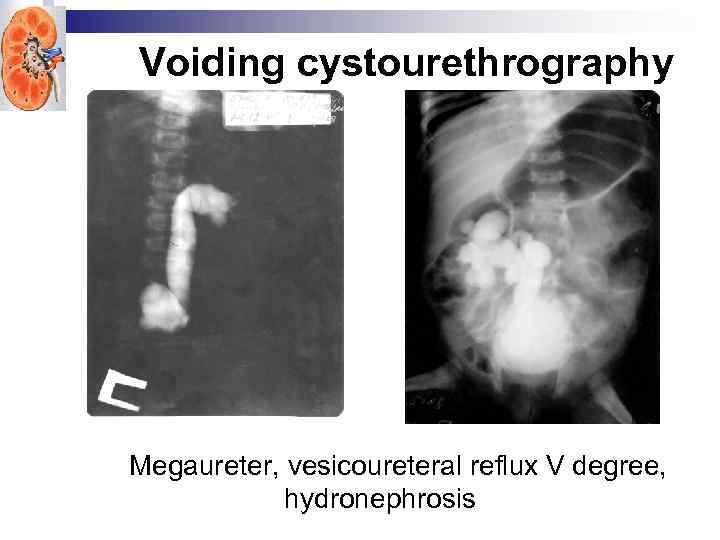

Voiding cystourethrography VUR is most often identified during radiologic evaluation following a UTI. The younger the patient with a UTI, the more likely VUR is present. No clinical signs are reliable in differentiating children with UTI with and without VUR. Diagnosis of reflux requires catheterization of the bladder, instillation of a solution containing iodinated contrast or a radiopharmaceutical, and radiologic imaging of the lower and upper urinary tract: a contrast VCUG or radionuclide cystogram (RNC), respectively. The bladder and upper urinary tracts are imaged during bladder filling and voiding.

Voiding cystourethrography VUR is most often identified during radiologic evaluation following a UTI. The younger the patient with a UTI, the more likely VUR is present. No clinical signs are reliable in differentiating children with UTI with and without VUR. Diagnosis of reflux requires catheterization of the bladder, instillation of a solution containing iodinated contrast or a radiopharmaceutical, and radiologic imaging of the lower and upper urinary tract: a contrast VCUG or radionuclide cystogram (RNC), respectively. The bladder and upper urinary tracts are imaged during bladder filling and voiding.

Voiding cystourethrography to diagnose VUR Advantages • • • Assesses the size and shape of bladder Detects and grades vesicoureteral reflux Evaluates posterior urethral anomalies in boys Disadvantages • Gonadal radiation • Catheterization

Voiding cystourethrography to diagnose VUR Advantages • • • Assesses the size and shape of bladder Detects and grades vesicoureteral reflux Evaluates posterior urethral anomalies in boys Disadvantages • Gonadal radiation • Catheterization

Voiding cystourethrography Megaureter, vesicoureteral reflux V degree, hydronephrosis

Voiding cystourethrography Megaureter, vesicoureteral reflux V degree, hydronephrosis